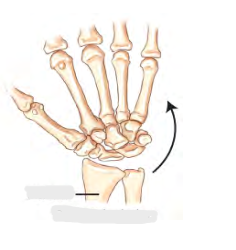

Image 2: Acute Flexion

Moving Fingers downwards wrist